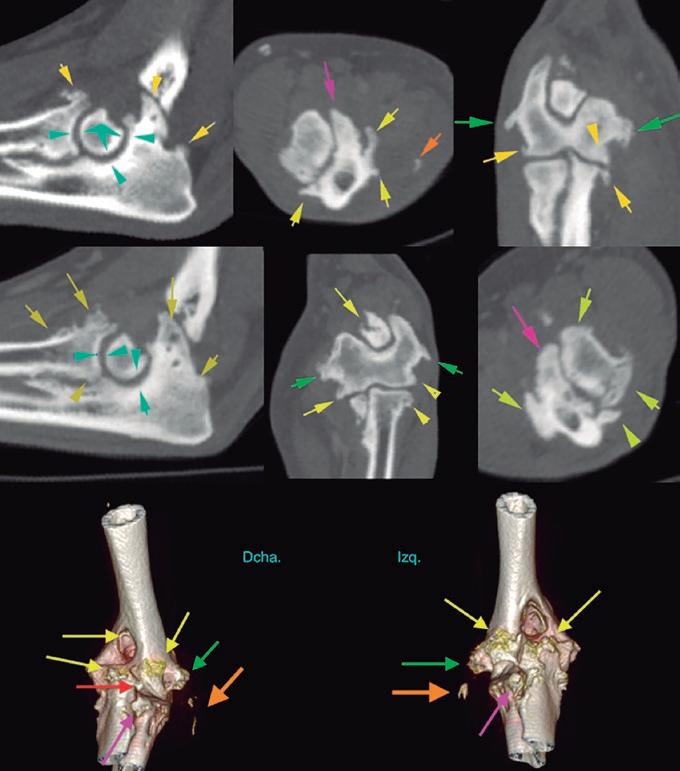

Para realizar la mayoría de los procedimientos quirúrgicos, es imprescindible disponer de un equipo de fluoroscopia, que permite la adquisición rápida de

La radiología intervencionista se realiza mediante un abordaje guiado por distintas técnicas de imagen como, por ejemplo, la ecografía, la fluoroscopia o la tomografía computarizada, para alcanzar la zona a diagnosticar o tratar.

La radiología intervencionista, también conocida como radiología vascular e intervencionista, es una especialidad que se encarga del diagnóstico y tratamiento de una gran cantidad de enfermedades de una manera mínimamente invasiva. Se realiza mediante un abordaje guiado por distintas técnicas de imagen como, por ejemplo, la ecografía, la fluoroscopia o la tomografía computarizada, para alcanzar la zona a diagnosticar o tratar.

La radiología vascular e intervencionista ofrece una alternativa segura y eficaz a la cirugía en muchas enfermedades. Entre sus ventajas para el paciente destaca una menor agresión a nivel tisular, una rápida recuperación, procedimientos sin dolor, rápidos y seguros, un menor coste respecto a otras muchas cirugías con mis-

imágenes basadas en rayos X y posteriormente las convierte en una señal de vídeo en tiempo real. Estas imágenes pueden manipularse ofreciendo funciones como la angiografía de sustracción digital, mapeo vascular y ampliación. Respecto a una radiografía, la exposición de rayos X necesaria para realizar una fluoroscopia es baja, pero debido a la duración de las series de imágenes que habitualmente se toman, el nivel de exposición en los pacientes suele ser elevado. Por lo tanto, es importante controlar el tiempo de exposición y llevar un registro de este. El fluoroscopio debe estar situado en una sala adecuada para su uso seguro, y todo el personal que entre en la sala de fluoroscopia debe protegerse de la radiación utilizando un delantal plomado, protectores de tiroides y gafas plomadas.

La radiología intervencionista es una especialidad que se encarga del diagnóstico y tratamiento de una gran cantidad de patologías de una forma mínimamente invasiva. Para realizar estos procedimientos es imprescindible disponer del equipamiento adecuado, tener nociones tanto de la instrumentalización como de las diferentes técnicas, y conocer con precisión la anatomía del paciente. Se trata de técnicas cada vez más implementadas en la clínica diaria ya que permiten solucionar diferentes patologías con una menor agresión a nivel tisular, una rápida recuperación, son procedimientos sin dolor, rápidos y seguros, suponen un menor coste respecto a otras cirugías invasivas, y constituyen una alternativa terapéutica a pacientes que no se pueden operar de forma convencional. Entre las más frecuentes destaca el cierre del conducto arterioso persistente, valvuloplastias en estenosis pulmonar, oclusión de shunts portosistémicos, implantación de marcapasos y colocación de stents